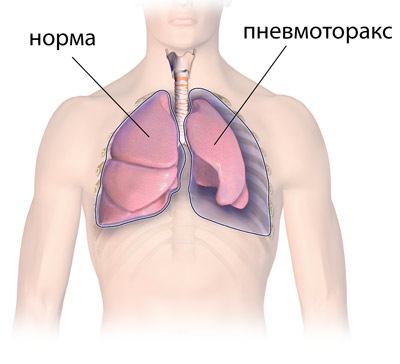

Схемы дыхания: Пневмоторакс на изображениях